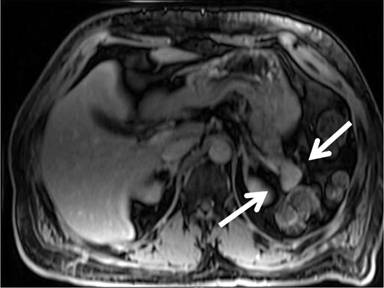

A 47-year-old African American male was admitted to the hospital for left chest wall abscess and diabetic ketoacidosis. Past medical history included diabetes mellitus type 1, essential hypertension, paroxysmal atrial fibrillation, ischemic stroke with minimal residual right sided paralysis, and chronic kidney disease. During the appropriate treatment of his admitting complaints, and management of his comorbidities, which included anticoagulation for the history of paroxysmal atrial fibrillation with CHADS score of 4, his hemoglobin dropped precipitously from 10 g/dL to 8.5 g/dL, then stabilized, then again dropped to 6.7 g/dL. Evaluation included esophagogastroduodenoscopy, which revealed fresh blood from second portion of duodenum, emanating from the ampulla (Figure 1). Contrast-enhanced MRI (Figure 2) showed a solid lesion within the pancreatic tail, measuring 1.8x1.5 cm, hyperenhancing and consistent with a pancreatic neuroendocrine tumor (PNET); there was no liver lesion identified. Endoscopic ultrasound (EUS) was concordant regarding size, shape, and location of the pancreatic lesion, and furthermore showed no stones, masses, or dilatation of the common bile duct (Figure 3). Biopsy of the pancreatic tumor was not performed due to concern for bleeding.

Figure 2. Early-arterial-enhanced nodule within pancreatic tail. Postcontrast VIBE image showing the enhancing nodule (arrows), with signal characteristics distinct from the spleen (not shown), precluding intrapancreatic splenule. |